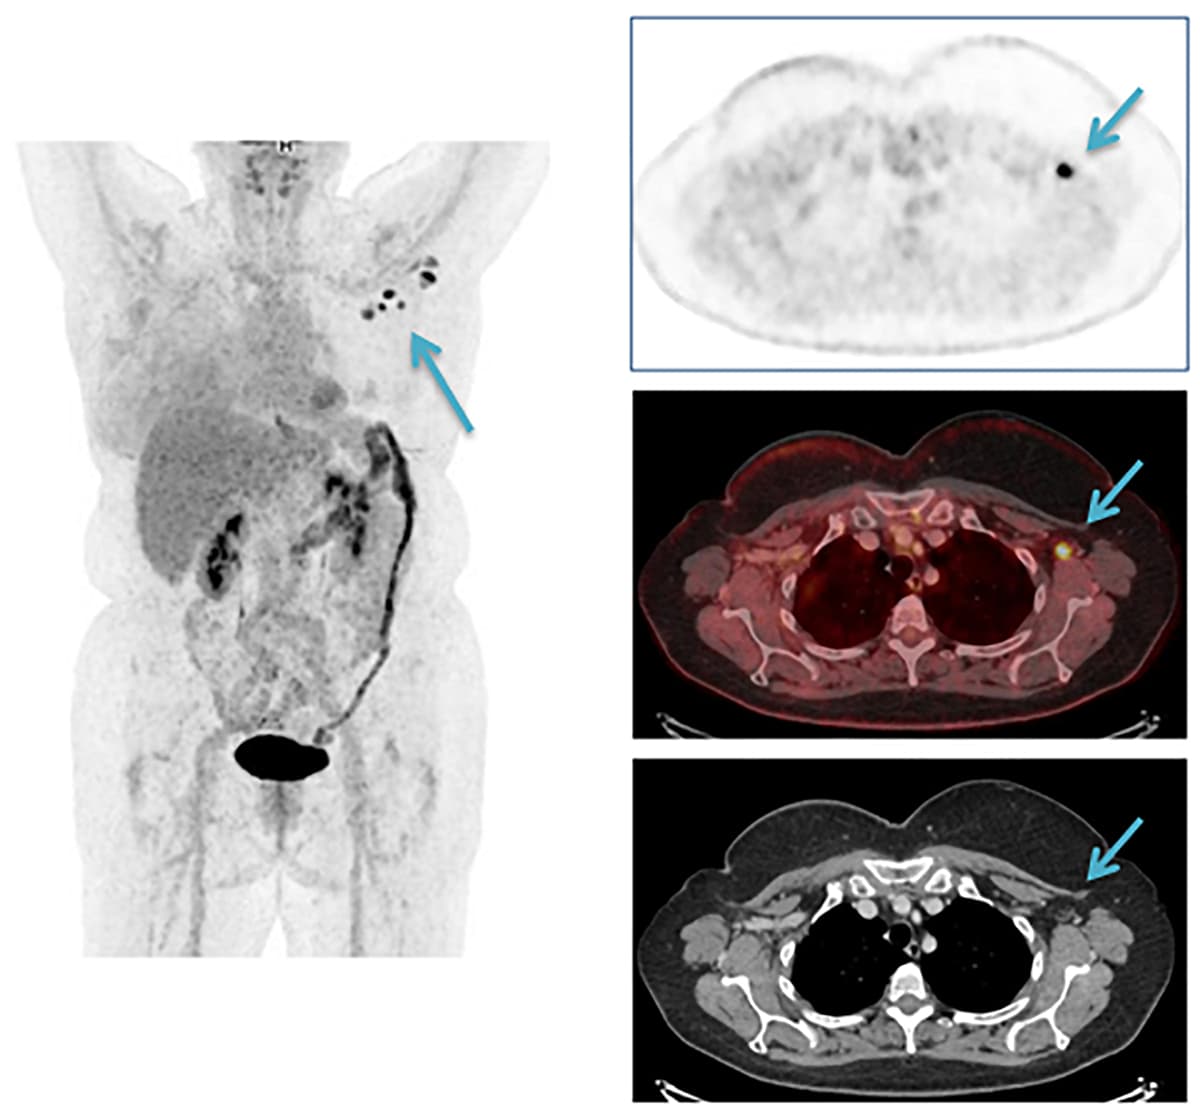

Patienten fik 11 dage efter vaccinationen udført en 18F-fluordeoxyglucose (FDG)-PET/CT, der viste flere små og forstørrede lymfeknuder med øget metabolisme i venstre aksil. En opfølgende UL-skanning 19 dage efter vaccinationen viste regression af de forstørrede lymfeknuder, hvoraf to med let asymmetrisk udseende finnålsaspireredes. Cytologien var uden malignitetsuspekte celler.

Reaktive lymfeknuder efter vaccination er velkendt [1] og også beskrevet som bivirkninger af vaccination mod COVID-19, herunder med vaccinen fra Pfizer BioNTech [2], men kan give anledning til differentialdiagnostiske overvejelser, særligt ved tolkning af 18F-FDG-PET/CT-billeder [3-5] hos patienter, der tidligere har haft cancer mammae, lymfom og malignt melanom.